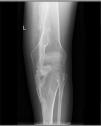

The patient was a 29-year-old woman, with a history of type 1A diabetes and primary amenorrhea secondary to cervical agenesis. At the age of 10 years, she was examined because she had developed a tumor in the cervical region, with no previous injury; she underwent a radiological study and bone biopsy that was compatible with myositis ossificans. Over the years, large ectopic ossifications developed in her shoulders, hips, knees, ankles and paravertebral muscles, which produced a marked secondary thoracolumbar scoliosis and a considerably generalized functional limitation. A plain radiology study of the affected areas showed the existence of exuberant bone bridges at different stages of maturation, that provoked the locking and ankylosing of a number of joints, including a knee (Fig. 1), the spine (Fig. 2) and a shoulder (Fig. 3). The patient was treated with bisphosphonates and calcium supplements with vitamin D for 5 years, while she was also being followed by the rehabilitation service; however, none of these measures was capable of arresting the course of the disease, which led to the physical disability of the patient.